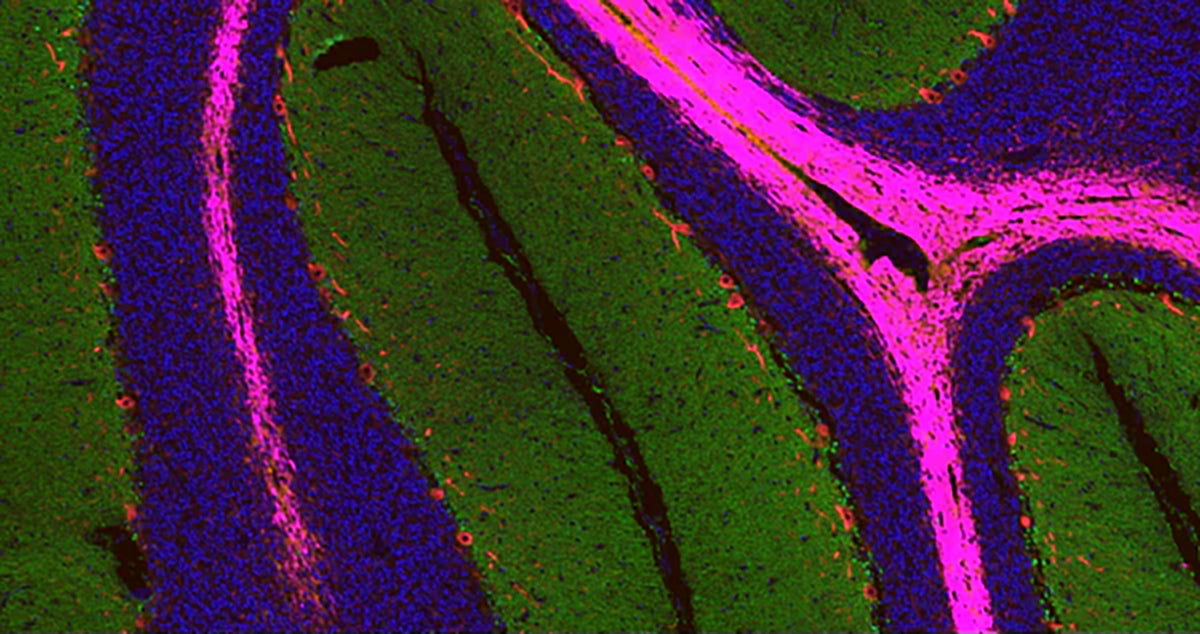

HRP Polymer Ready-To-Use Kits

The provided HRP polymer conjugated secondary antibody significantly address the limitations commonly experienced with traditional immunohistochemistry (IHC) methods, such as poor or inconsistent antigen staining when identifying low-abundance antigens or in situations of suboptimal antibody-antigen binding.

By utilizing an HRP polymer conjugate, the sensitivity of detection is dramatically increased and the process is simplified.Moreover, the HRP polymer-based amplification method reduces the amount of primary antibody needed and shortens the secondary antibodies’ incubation period.